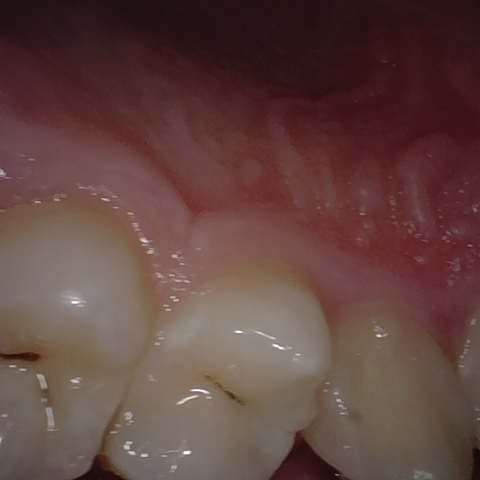

Incorrect Quality Level

The reference annotation for this image is

None

.

Please select the correct quality level.

Annotated as "Good"